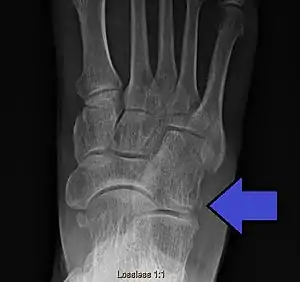

| Avulsion fracture of the right cuboid bone of the foot | |